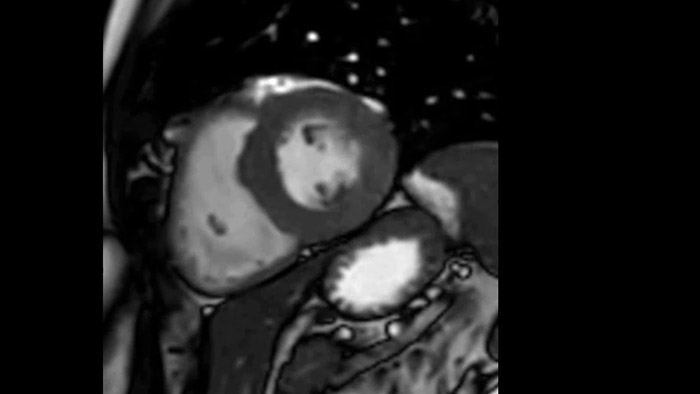

Os diagnósticos tradicionais não têm a visibilidade necessária para ver os efeitos do tratamento cardíaco ou para detetar disfunção antes que os sintomas ocorram. Ao combinar a sequência de aquisição de RM da Philips Fast-SENC com a ferramenta de análise MyoStrain da Myocardial Solutions, as alterações precoces e subtis da função cardíaca podem ser medidas diretamente.

O IntelliSpace Portal MR Caas7,8 Strain9 ajuda no diagnóstico e monitorização do paciente ao proporcionar parâmetros globais de deformação, tais como deformação longitudinal global (GLS), deformação circunferencial global (GCS) e deformação radial global (GRS), utilizando imagens de RM de eixo curto e longo, bem como descrevendo a deformação do miocárdio, como encurtamento, espessamento e alongamento durante o ciclo cardíaco.